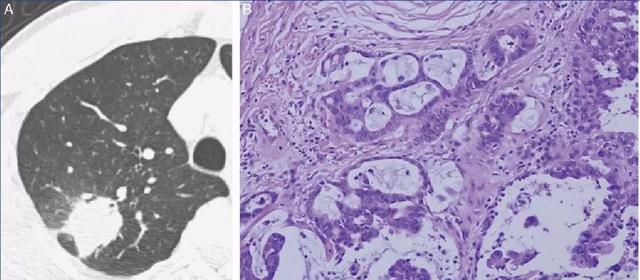

2.微浸润腺癌

10~15mm。如果在原位癌的阶段没有注意戒烟健康的生活方式。原来就会继续增长扩大,此时叫微浸润癌。此时癌症已经长大超过10个毫米。内部可以没有实性成分,是纯磨玻璃结节,也可以出现5个毫米以内的实性成分。此时癌细胞还没有侵犯到胸膜,血管,淋巴管,仍然是早期肺癌。

3.浸润性腺癌

大于15毫米。此时癌细胞继续增多增大,结节出现了明显的实性成分,并且突破了支气管的基底膜长到了血管和淋巴管里面去。